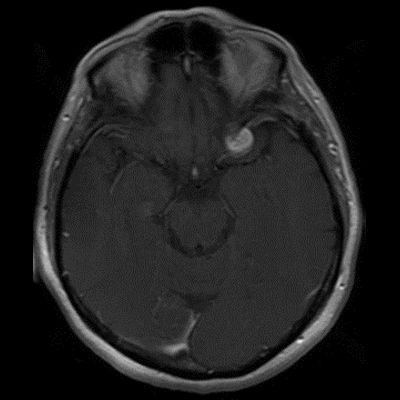

60 yaş, K

Baş ağrısı

Tanınız nedir?